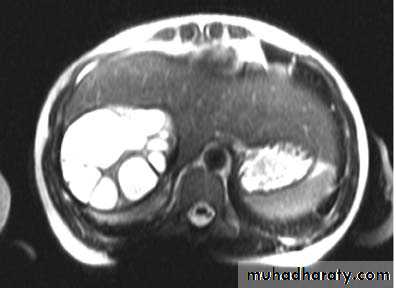

Hemangioma